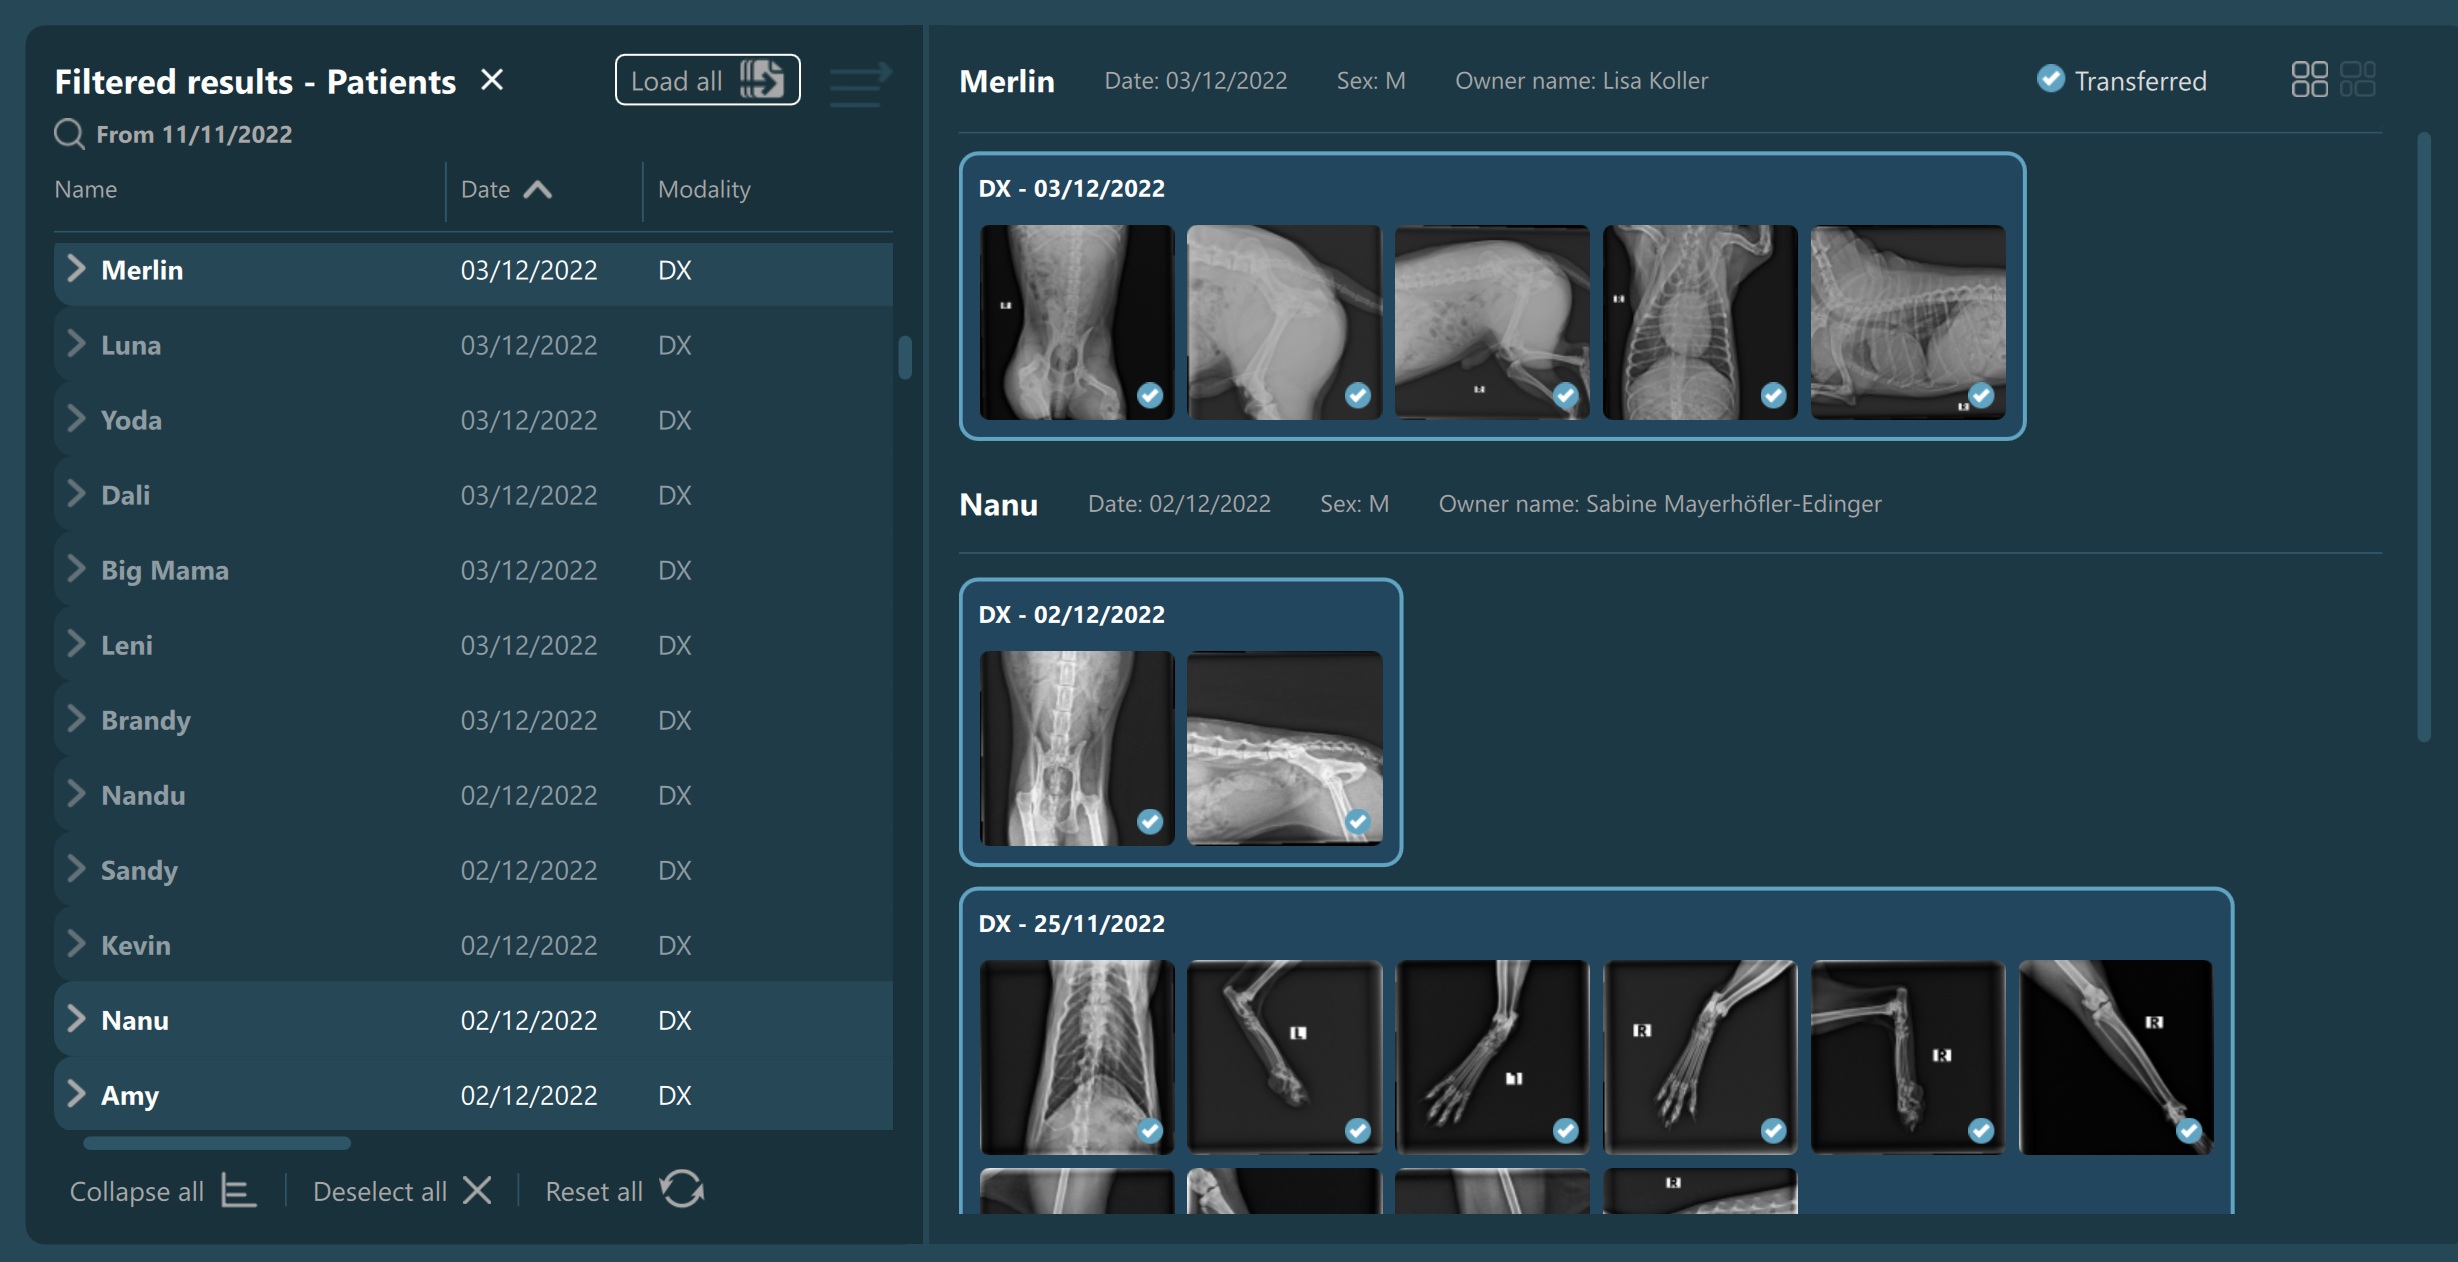

Selecting a patient, study, or series from the Study List opens them and their contents in the Preview Pane, located on the right side of the Study Browser window. In the Preview Pane, the items are separated into sections based on their patient information.

The heading of each section shows the patient name, the latest related study date, patient sex, and owner name. Studies are shown as image groups containing the series as image previews. Each study is highlighted by its modality and date. To view the series description of each series, hover over the desired image preview.

The top right corner of the Preview Pane offers the users the ability to switch the thumbnail preview between unified or keeping the original aspect ratio of the image.

Additionally, if the selected server was configured to allow users to manually download images, the Transfer button is also available in the Preview Pane. More information on image transfers can be

Similar to the selection in the Study List, users have the ability to select patients, studies, or individual series. A highlighted selection in the Preview Pane indicates the active selection in the Study List.

The Preview Pane can also be used to extend or narrow down the selection from the Study List. To select/deselect items in the Preview Pane simply press on them with the mouse.

Additionally, when images are being transferred, a Transferring… label is shown in the heading of the Preview Pane. Moreover, each series in the Preview Pane has its own state indicating whether the transfer is ongoing or it has finished. When all of the selected images have been transferred, the label in the heading of the Preview Pane is changed to Transferred as well.

Transfer of images has been completed: